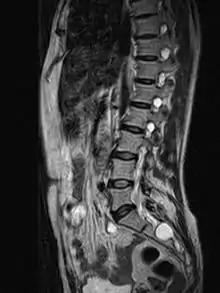

MRI image showing a Tarlov cyst

MRI

MRI sagittal image of sacral and dorso-lumbar perineural cysts.

MRI, or Magnetic Resonance Imaging, is considered the imaging study of choice in identifying Tarlov cysts. MRI provides better resolution of tissue density, absence of bone interference, multiplanar capabilities, and is noninvasive. Plain films may show bony erosion of the spinal canal or of the sacral foramina. On MRI pictures, the signal is the same as the CSF one.